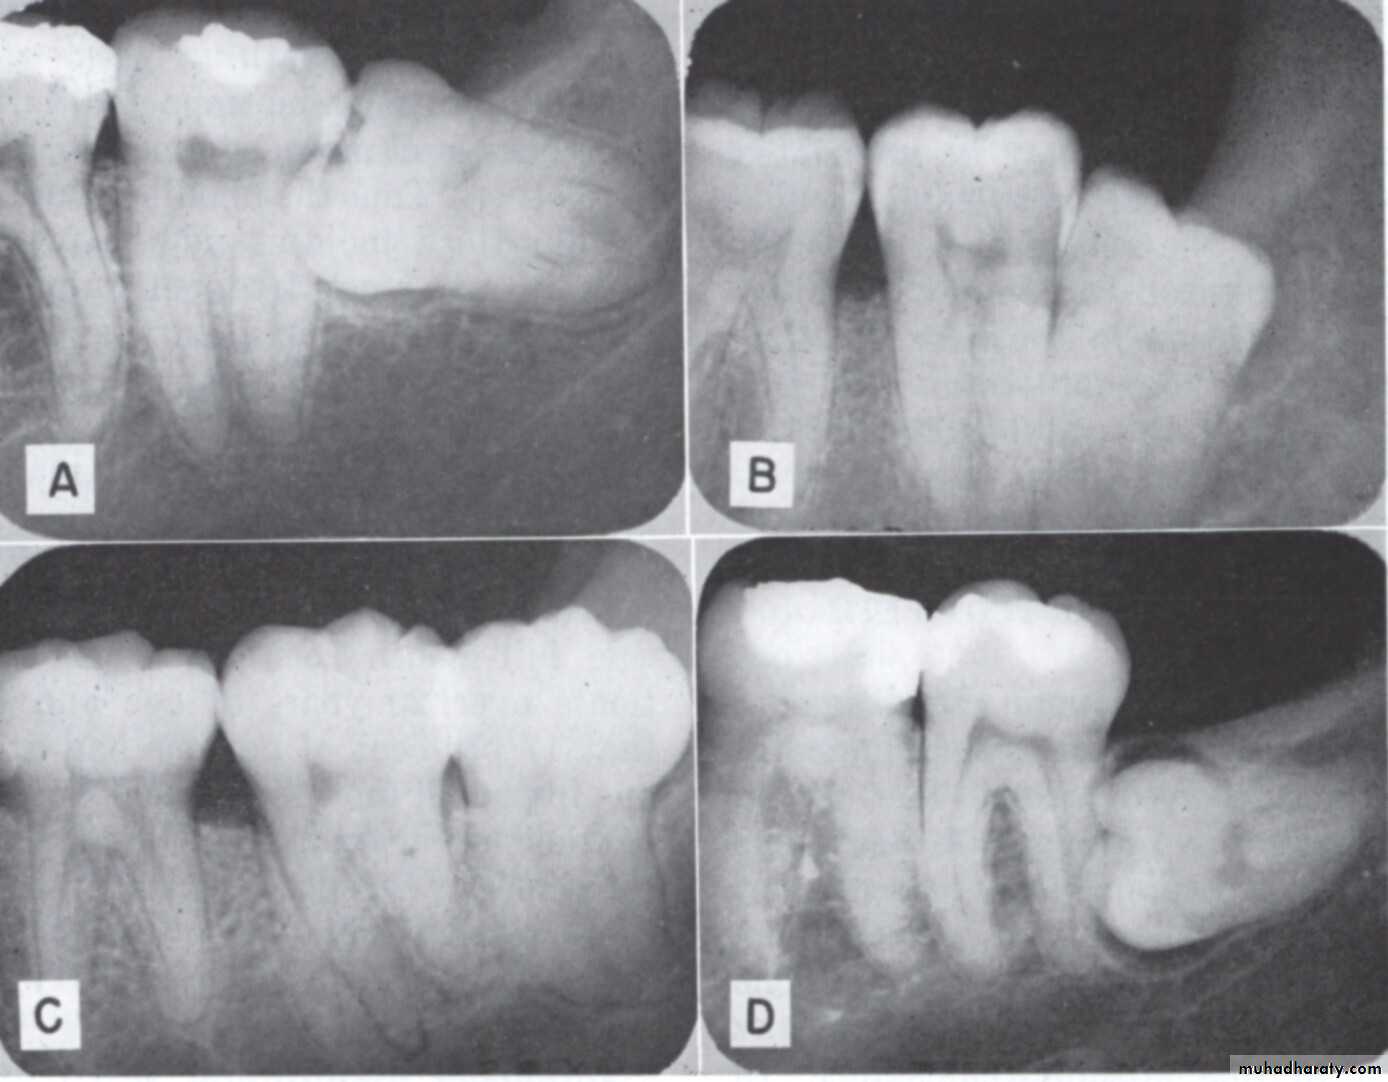

This is characterized by dull pain or mild discomfort lasting for only a day and interspersed with remissions lasting many months . The patient usually complain of unpleasant taste . A crater like defect may be seen in the radiograph of the area .2 – prevention of Dental caries

Dental caries can occur at the lower 8 oradjacent lower 7 most commonly at the

cervical line due to the inability of the patient

to clean the area thoroughly .

3 - Prevention of Periodontal disease

Food debris accumulation distal to the second molar and difficulty to clean it may lead to periodontal problems4-Prevention of resorption of adjacent tooth root

If external resorption is small in amount the tooth may repair it self by deposition of a layer of cementum over the resorbed area and the formation of secondary dentin . But if the resorption is severe both second and third molar may require removal .